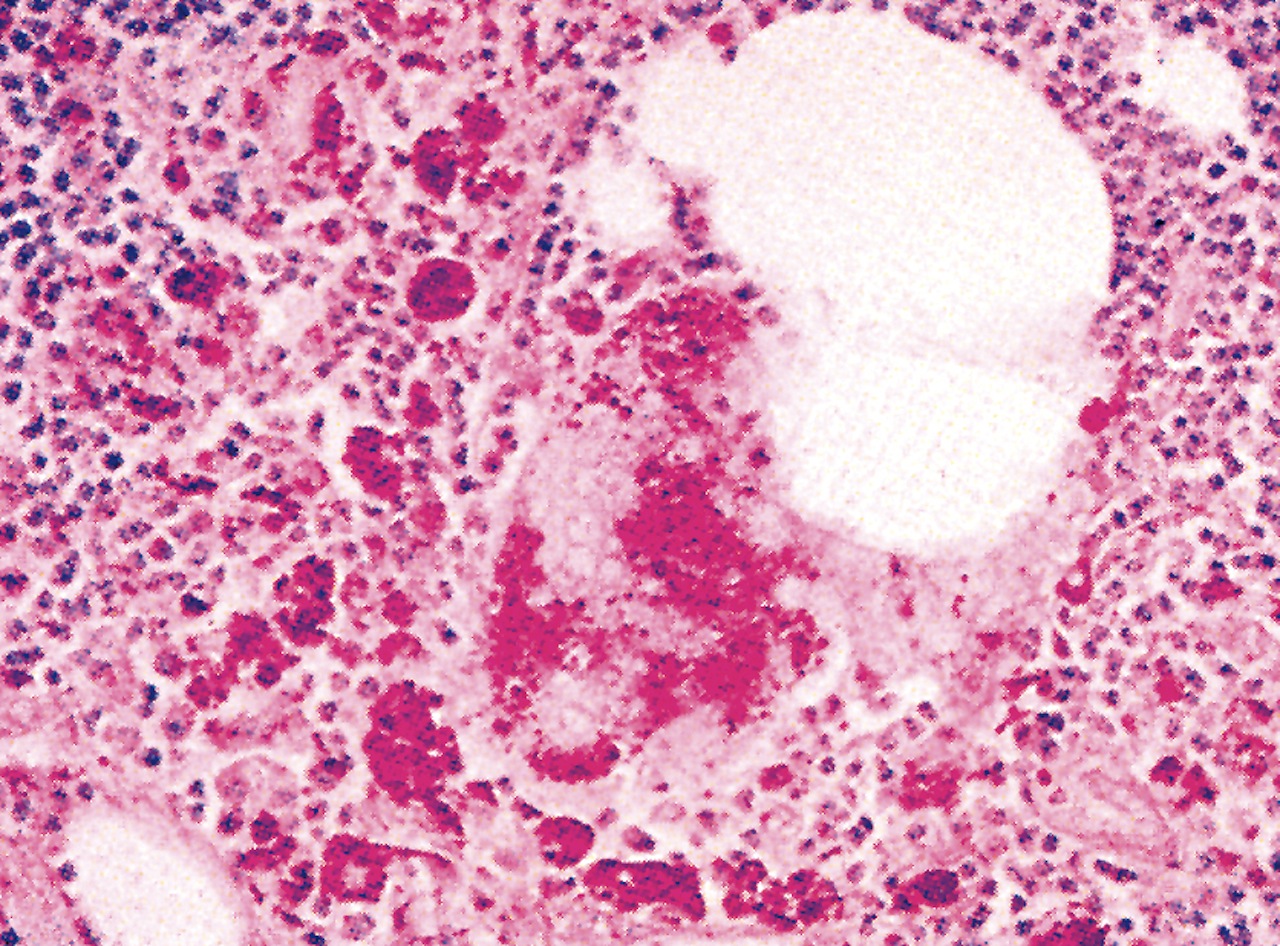

Microscopic (histologic) description

- Focal nodal effacement by multiple coalescing intranodal clusters of small blood vessels, lined by epithelioid endothelial cells with pale cytoplasm

- May have focal nuclear atypia

- Interstitium contains abundant eosinophilic to amphophilic, amorphous or granular material containing aggregates of bacteria (highlighted by Warthin-Starry stain)

- Also neutrophils

- Post vaccination bacille Calmette-Guerin infection occurs in 1% of infants, although swelling usually subsides (Braz J Med Biol Res 2004;37:697)BACILLARY ANGIOMATOSIS Left: Proliferated blood vessels are separated by abundant eosinophilic, vaguely fibrillary material. Some neutrophils are also seen. Right: Barely canalized blood vessels separated by eosinophilic interstitial materials in the absence of neutrophils.